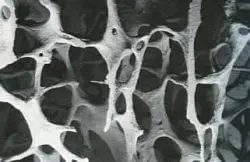

Соли кальция, поступающие в организм с пищей и биологическими добавками, поддерживают целостность костей. При этом часть питательных веществ вымывается. У здорового человека процессы образования и рассасывания костной ткани сбалансированы. При остеопорозе разрушение преобладает над восстановлением (см. рисунки ниже: рис.1. норма, 2 — остеопороз). Это приводит к повышению хрупкости костей.

Кость состоит из костных балок. При остеопорозе их количество уменьшается, они истончаются вплоть до рассасывание участков кости. Суть остеопороза заключается в ускоренном вымывании солей кальция из кости.

| Рис. 1. Анатомический препарат тела позвонка. Неизмененная кость с нормальной плотностью | Рис. 2. Анатомический препарат тела позвонка. Видны Начальный остеопороз костей: трабекулы истончены, межтрабекулярные пространства увеличены. |

| Рис. 3. Неизмененная (без остеопороза) костная ткань под микроскопом. | Рис. 4. Измененная костная ткань с признаками остеопороза под микроскопом. |